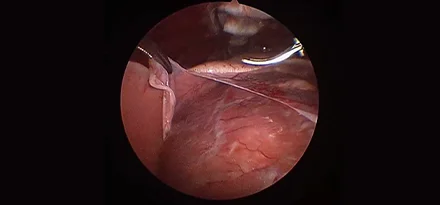

흉강경심막절제술 (Preicardiectomy)

흉강경흉관결찰 (Thoracic duct ligation)

* 리본동물의료센터 케이스 사진으로 무단 복제 및 도용을 금지합니다.